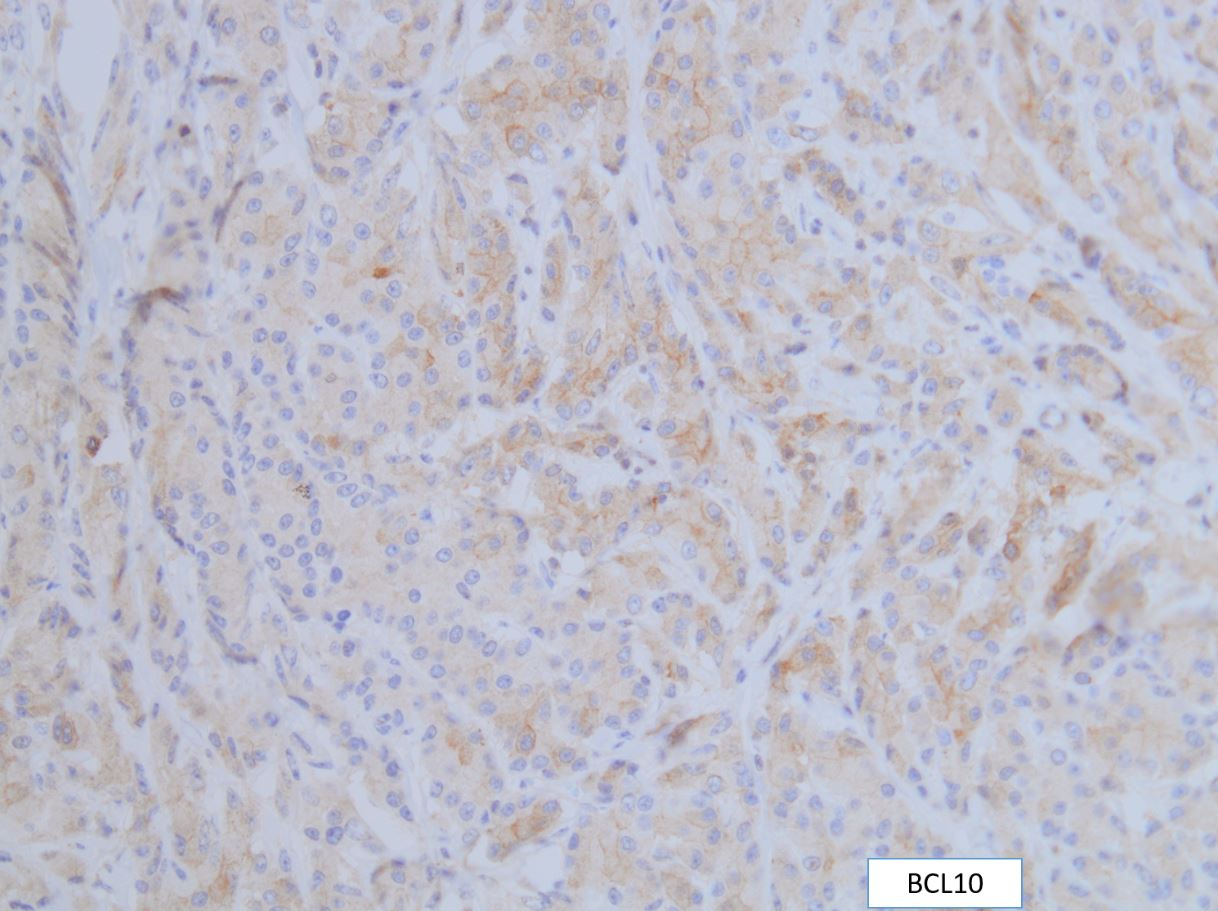

A 75-year-old woman with suspected pancreatic NET undergoes a Whipple. The morphology of the tumor is seen in Fig A-D. A synaptophysin is performed (Fig E). What additional IHC profile can be expected in this tumor?

“C.” Trypsin (+), BCL10 (+)

The tumor is solid and cellular with the individual cells displaying abundant granular cytoplasm and round monotonous nuclei with prominent nucleoli, configured in a vague acinar formation. These features are consistent with an acinar cell carcinoma, therefore positive staining for trypsin and BCL10 are expected (figures).